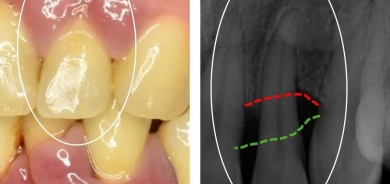

علاقة أمراض اللثة بمرض ألزهايمر

ما أسباب الالتهابات الحادة للثة؟